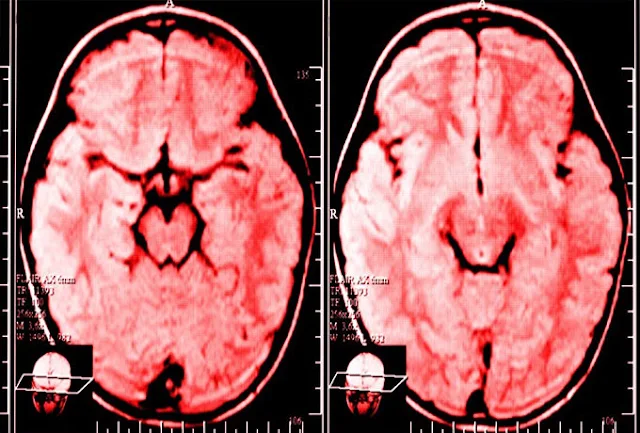

Благодаря полученным за последние двадцать лет знаниям в области нейробиологии, а также быстрому развитию технологий сканирования мозга, теперь мы может с полной уверенностью сказать, что мозг способен на довольно значительную перестройку своих функций, и мы выступаем в роли архитекторов и исполнителей этой перестройки.

В общем и целом, нейропластичность — термин, характеризующий способность мозга вносить в свою структуру долговременные изменения.